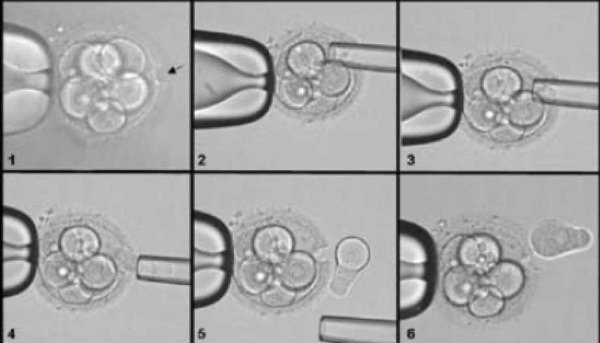

טכנולוגיה זו נכנסה לשימוש עבור מחלות גנטיות קשות, כדי למנוע העברת שינויים גנטיים חמורים בתורשה [11]. בהליך מבוצעת הפריה חוץ גופית שבה נבדקים העוברים טרם החזרתם לרחם, לנשאיות המוטציה (תמונה מס' 3). בדיקה זו אינה פוגעת בעוברים, וכך ניתן לבחור את העוברים שאינם נושאים את השינוי הגנטי ולהבטיח כי הם לא יישאו את המוטציה הגנטית. הליך זה מעניק שקט נפשי לנשאים. עם זאת, עומדת בפני כל משפחה בחירה חופשית אם לבצעו או לא, וחלק מהמשפחות בוחרות שלא לבצעו. טכנולוגיה זו נמצאת בסל הבריאות לחולים בפוליפוזיס משפחתי ודורשת מוטציה מזוהה. המרכזים הרפואיים בארץ המבצעים אבחנה טרום-השרשתית הם תל אביב ע"ש סוראסקי, רבין, שערי צדק והדסה.

1. חירור המעטפת Zona pellucida של טרום־עובר בן שמונה תאים באמצעות קרן לייזר

2,3. החדרת פיפטה דקה לתוך טרום־העובר ויצירת מגע עם אחד הבלטטומרים.

4. משיכת הבלסטומר הבודד באמצעות מערכת מיקרומניפולציה,

5. שחרור התא הבודד מחוץ לטרום־עובר,

6. התא מוכן לאיטוף (בנפרד מטרום־העובר) לצורך אבחונו הגנטי.